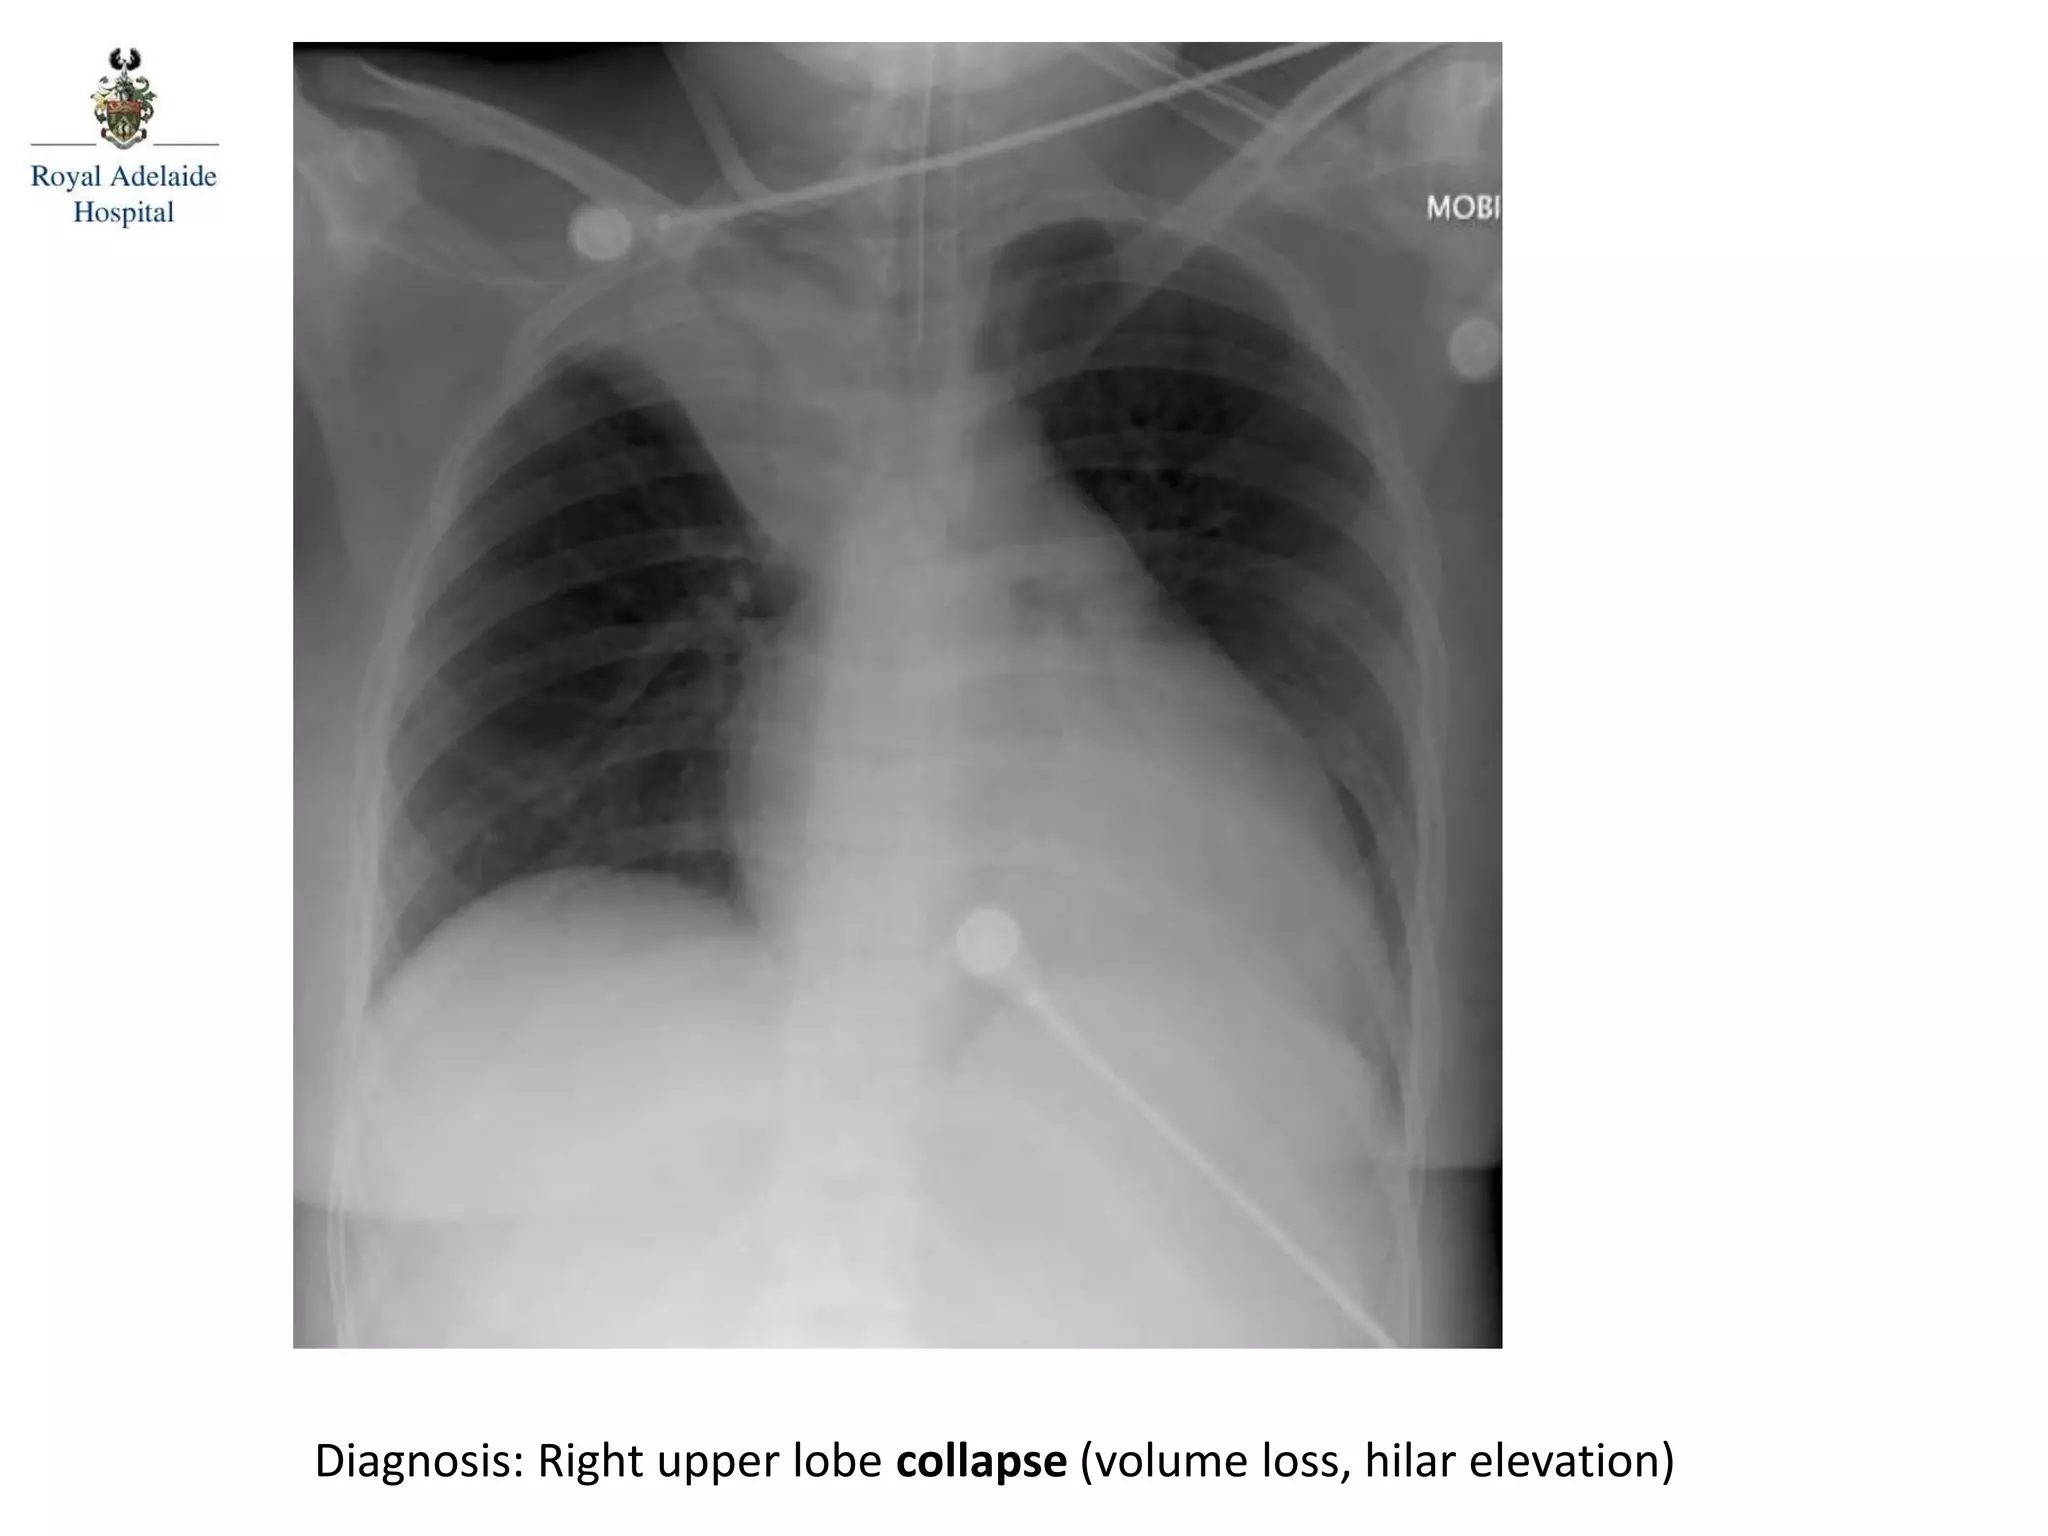

Diagnosis: Right upper lobe collapse (volume loss, hilar elevation)